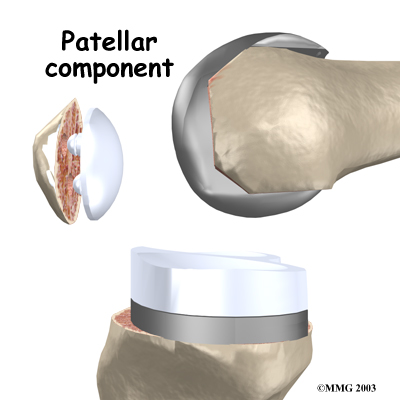

The tibial component (bottom portion) replaces the top surface of the lower bone, the tibia. The femoral component (top portion) replaces the bottom surface of the upper bone (the femur) and the groove where the patella fits. The patellar component (kneecap portion) replaces the surface of the patella where it glides in the groove on the femur.

The femoral component is made of metal. The tibial component is usually made of two parts: a metal tray that is attached directly to the bone, and a plastic spacer that provides the slick surface. The plastic used is so tough and slick that you could ice skate on a sheet of it without damaging the material much. The patellar component is usually made of plastic as well. In some types of knee implants, the patellar component is made of a combination of metal and plastic.

The surgeon then sizes the patellar component andd puts it into place behind the patella. This piece is usually cemented in place.

Patellar Component

View animation of removing the patella and inserting the patellar component: